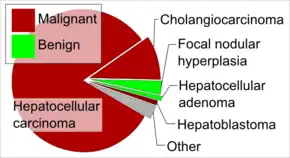

The most common malignant tumors in the liver represent metastases (spread) from tumors which originate elsewhere in the body.[83] Among cancers that originate from liver tissue, HCC is the most common primary liver cancer. In the United States, the US surveillance, epidemiology, and end results database program, shows that HCC accounts for 65% of all cases of liver cancers.[85] As screening programs are in place for high-risk persons with chronic liver disease, HCC is often discovered much earlier in Western countries than in developing regions such as sub-Saharan Africa.